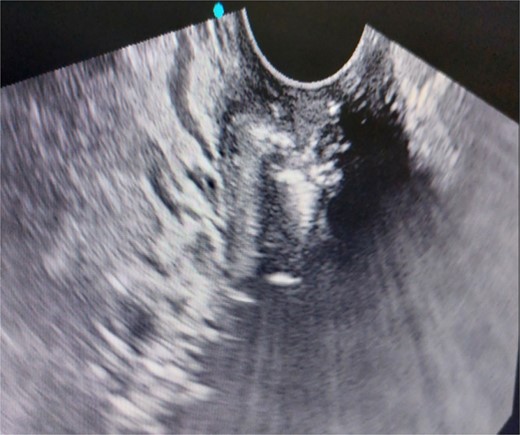

A 26-year-old nulliparous lady from a rural area was referred to emergency from a primary health care centre with a failed attempt to remove an impacted uterine foreign body. On per speculum examination, an impacted hard pipe-like structure was protruding from the cervix. The patient gave a history of foreign body insertion 9 years back, however, failed to provide a detailed account of the mode of insertion or history of sexual assault. She went to seek medical care only after developing profuse foul-smelling discharge and chronic pelvic pain. Removal was attempted under local anaesthesia but failed. Transvaginal scan showed a bulky uterus with an apparently normal endometrial thickness and echotexture; however, the cervical canal was distended with an echogenic area and areas of calcification (Figs 1 and 2). She was taken up for removal of the foreign body under general anaesthesia. As a hard pipe-like structure was already protruding, removal was tried by grasping it with a Kocher’s forceps. After multiple attempts part of the foreign body was removed. Hysteroscopy showed that the lower endocervical canal was clear and a ring-like structure occupied the upper endocervical canal. Removal under direct vision using a hysteroscopic grasper was attempted but failed due to the impaction and size of the object and the hysteroscope could not be negotiated beyond the object. A laparotomy was performed and after an assessment of anatomy and tactile sensation to assess accessibility, incision on the posterior surface of the uterus was given (Figs 3 and 4) and the object was removed (Fig. 5). The incision was closed in two layers. Intercede was placed at the repair site. An extended course of antibiotics was given for 7 days. Post-operative recovery was uneventful. Contraception for at least 1 year, the need for proper antenatal care, the risk of rupture, and mandatory caesarean delivery were counselled to the couple.